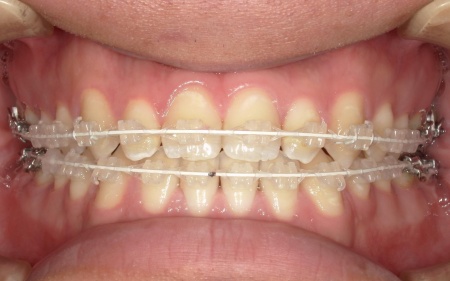

20代男性 受け口のように見える切端咬合をセラミックブラケットによる矯正治療で改善した症例

拝見したところ、上下前歯の先端同士が触れ合う「切端咬合(せったんこうごう)」の状態でした。

通常は上前歯が下前歯をわずかに覆うように重なりますが、患者様の場合は上下前歯の先端がほぼ同じ高さで噛み合っているため、受け口のような印象がみられました。

患者様は「できるだけ目立ちにくい装置を使用したい」とのことから、②のセラミックブラケット矯正を選択されました。

加えて、上下の前歯には「IPR」という処置を行いました。これは、歯の表面のエナメル質をごくわずかに削り、歯を動かすためのスペースを作る方法です。

このスペースを利用して前歯を後方へ移動させ、審美性の改善を目指しました。

最後に、歯並びと噛み合わせが整い、見た目にも問題がないことを確認し、治療を終了しています。